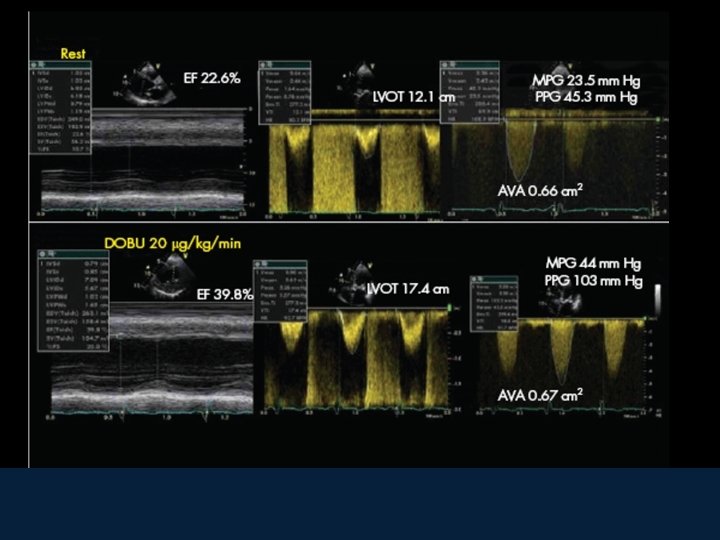

Aortic Stenosis: valvular area with continuity equation Continuity equation: equal istantaneal flow through left ventricular outflow tract (LVOT) and the aortic valve Flow LVOT = Flow Ao V VTI AO VTI LV Ao LVOT LA Flow = area (3. 14 x (D/2)² x Integral time velocity Doppler (ITV) Area LVOT (3. 14 x (D/2)² x Integral time velocity Doppler (ITV LVOT) = Area Ao V (3. 14 x (D/2)² x Integral time velocity Doppler (ITV Ao V) Aortic Valve area = 3. 14 x (D/2)² x (ITV LVOT / ITV Ao V)

Classification of severty of Valve Disease in Adults